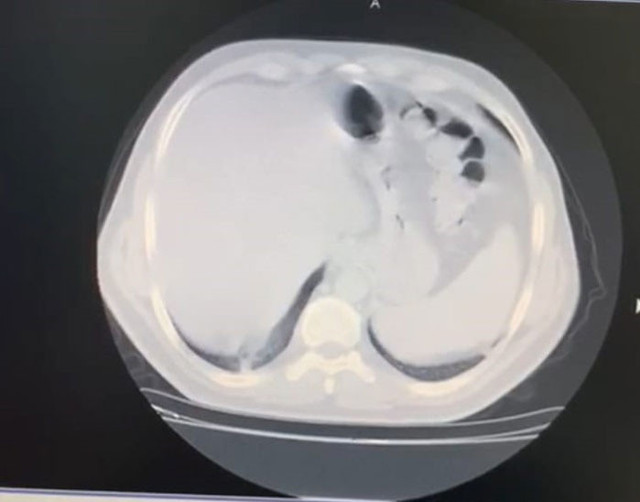

Abone olYoğun kas ağrısı şikayeti olan İç Hastalıkları Uzmanı Celal Civil, akciğer tomografisinin ardından koronavirüse yakalandığını fark etti. 8 gün evde tedavi gören Civil’in durumu kötüye gitmeye başladı. İkinci tomografisinde koronavirüsün akciğerinin yüzde 70’ini kapladığı görülen genç doktor, yaklaşık 1 aylık tedavisinin ardından sağlığına kavuşarak görevine döndü.

Evdeki 8 günlük sürecin ardından durumu ağırlaşan Civil, ikinci kez çekilen tomografide akciğerinde yaygın bir koronavirüs zatürre tutulumu görüldüğüne dikkat çekerek şunları söyledi;

“Çok korkunç bir görüntü vardı. O görüntüyü görünce psikolojik olarak da çok etkilendim. Daha sonra hastaneye yatırıldım ve ateşim 41 derece civarındaydı. Oksijen satürasyonum da 70’lere kadar düştü. Yoğun bakım hastalarında kullanılan bir ilaca başlandı. Hastaneye yattığımın ilk 3 günü çok kritikti. Genel durumum bu 3 gün içerisinde yavaş yavaş bozulmaya başlamıştı. Nefes alamıyordum ve boğuluyordum. Sıkıntılı ve sancılı bir süreçti"

Bulguların ne anlama geldiğini biliyordum: Ümitsizliğe kapıldım